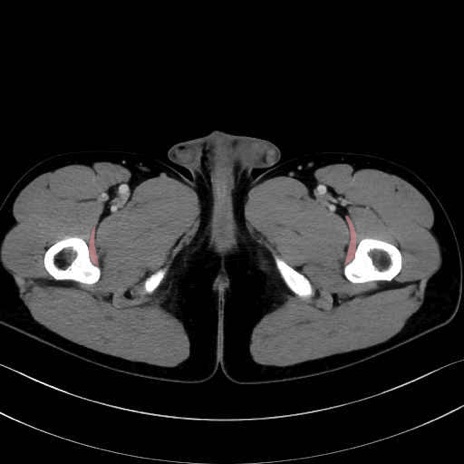

腸骨筋 (Iliacus)